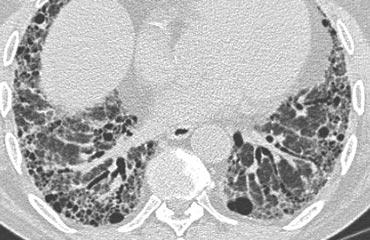

Đây là một trường hợp sarcoidosis phế nang.

Hình ảnh trông giống như tăng tỷ trọng dạng kính mờ, nhưng khi quan sát kỹ hơn có thể nhận thấy rằng sự tăng tỷ trọng này là kết quả của nhiều nốt nhỏ tập hợp lại.

Cũng lưu ý hạch to rốn phổi.